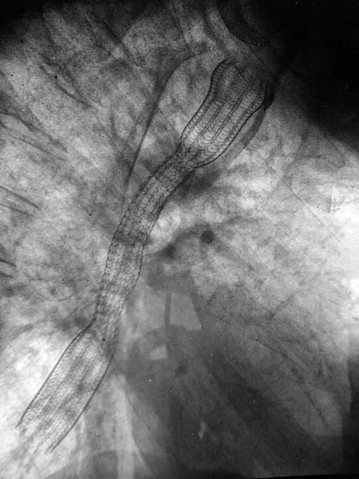

If operation is inappropriate, oesophageal patency can often be restored by palliative ablation of the tumour with laser therapy or argon plasma coagulation via a gastroscope. These treatments can be repeated as the tumour regrows. Alternatively, the oesophagus can be intubated with an expanding metal stent (see Fig. 22.4) through the lesion. This is usually done under intravenous sedation, using the endoscopic technique of pulsion intubation. First the oesophageal lesion is dilated then the stent inserted using X-ray guidance. These tubes relieve symptoms, but food has to be liquidised and the tube kept ‘clean’ by taking fizzy drinks after eating. Patients are more susceptible to acid reflux, for which antacid medication may need to be prescribed. Chemotherapy, external beam radiotherapy and intraluminal brachytherapy (local radiotherapy) are increasingly used for palliation.